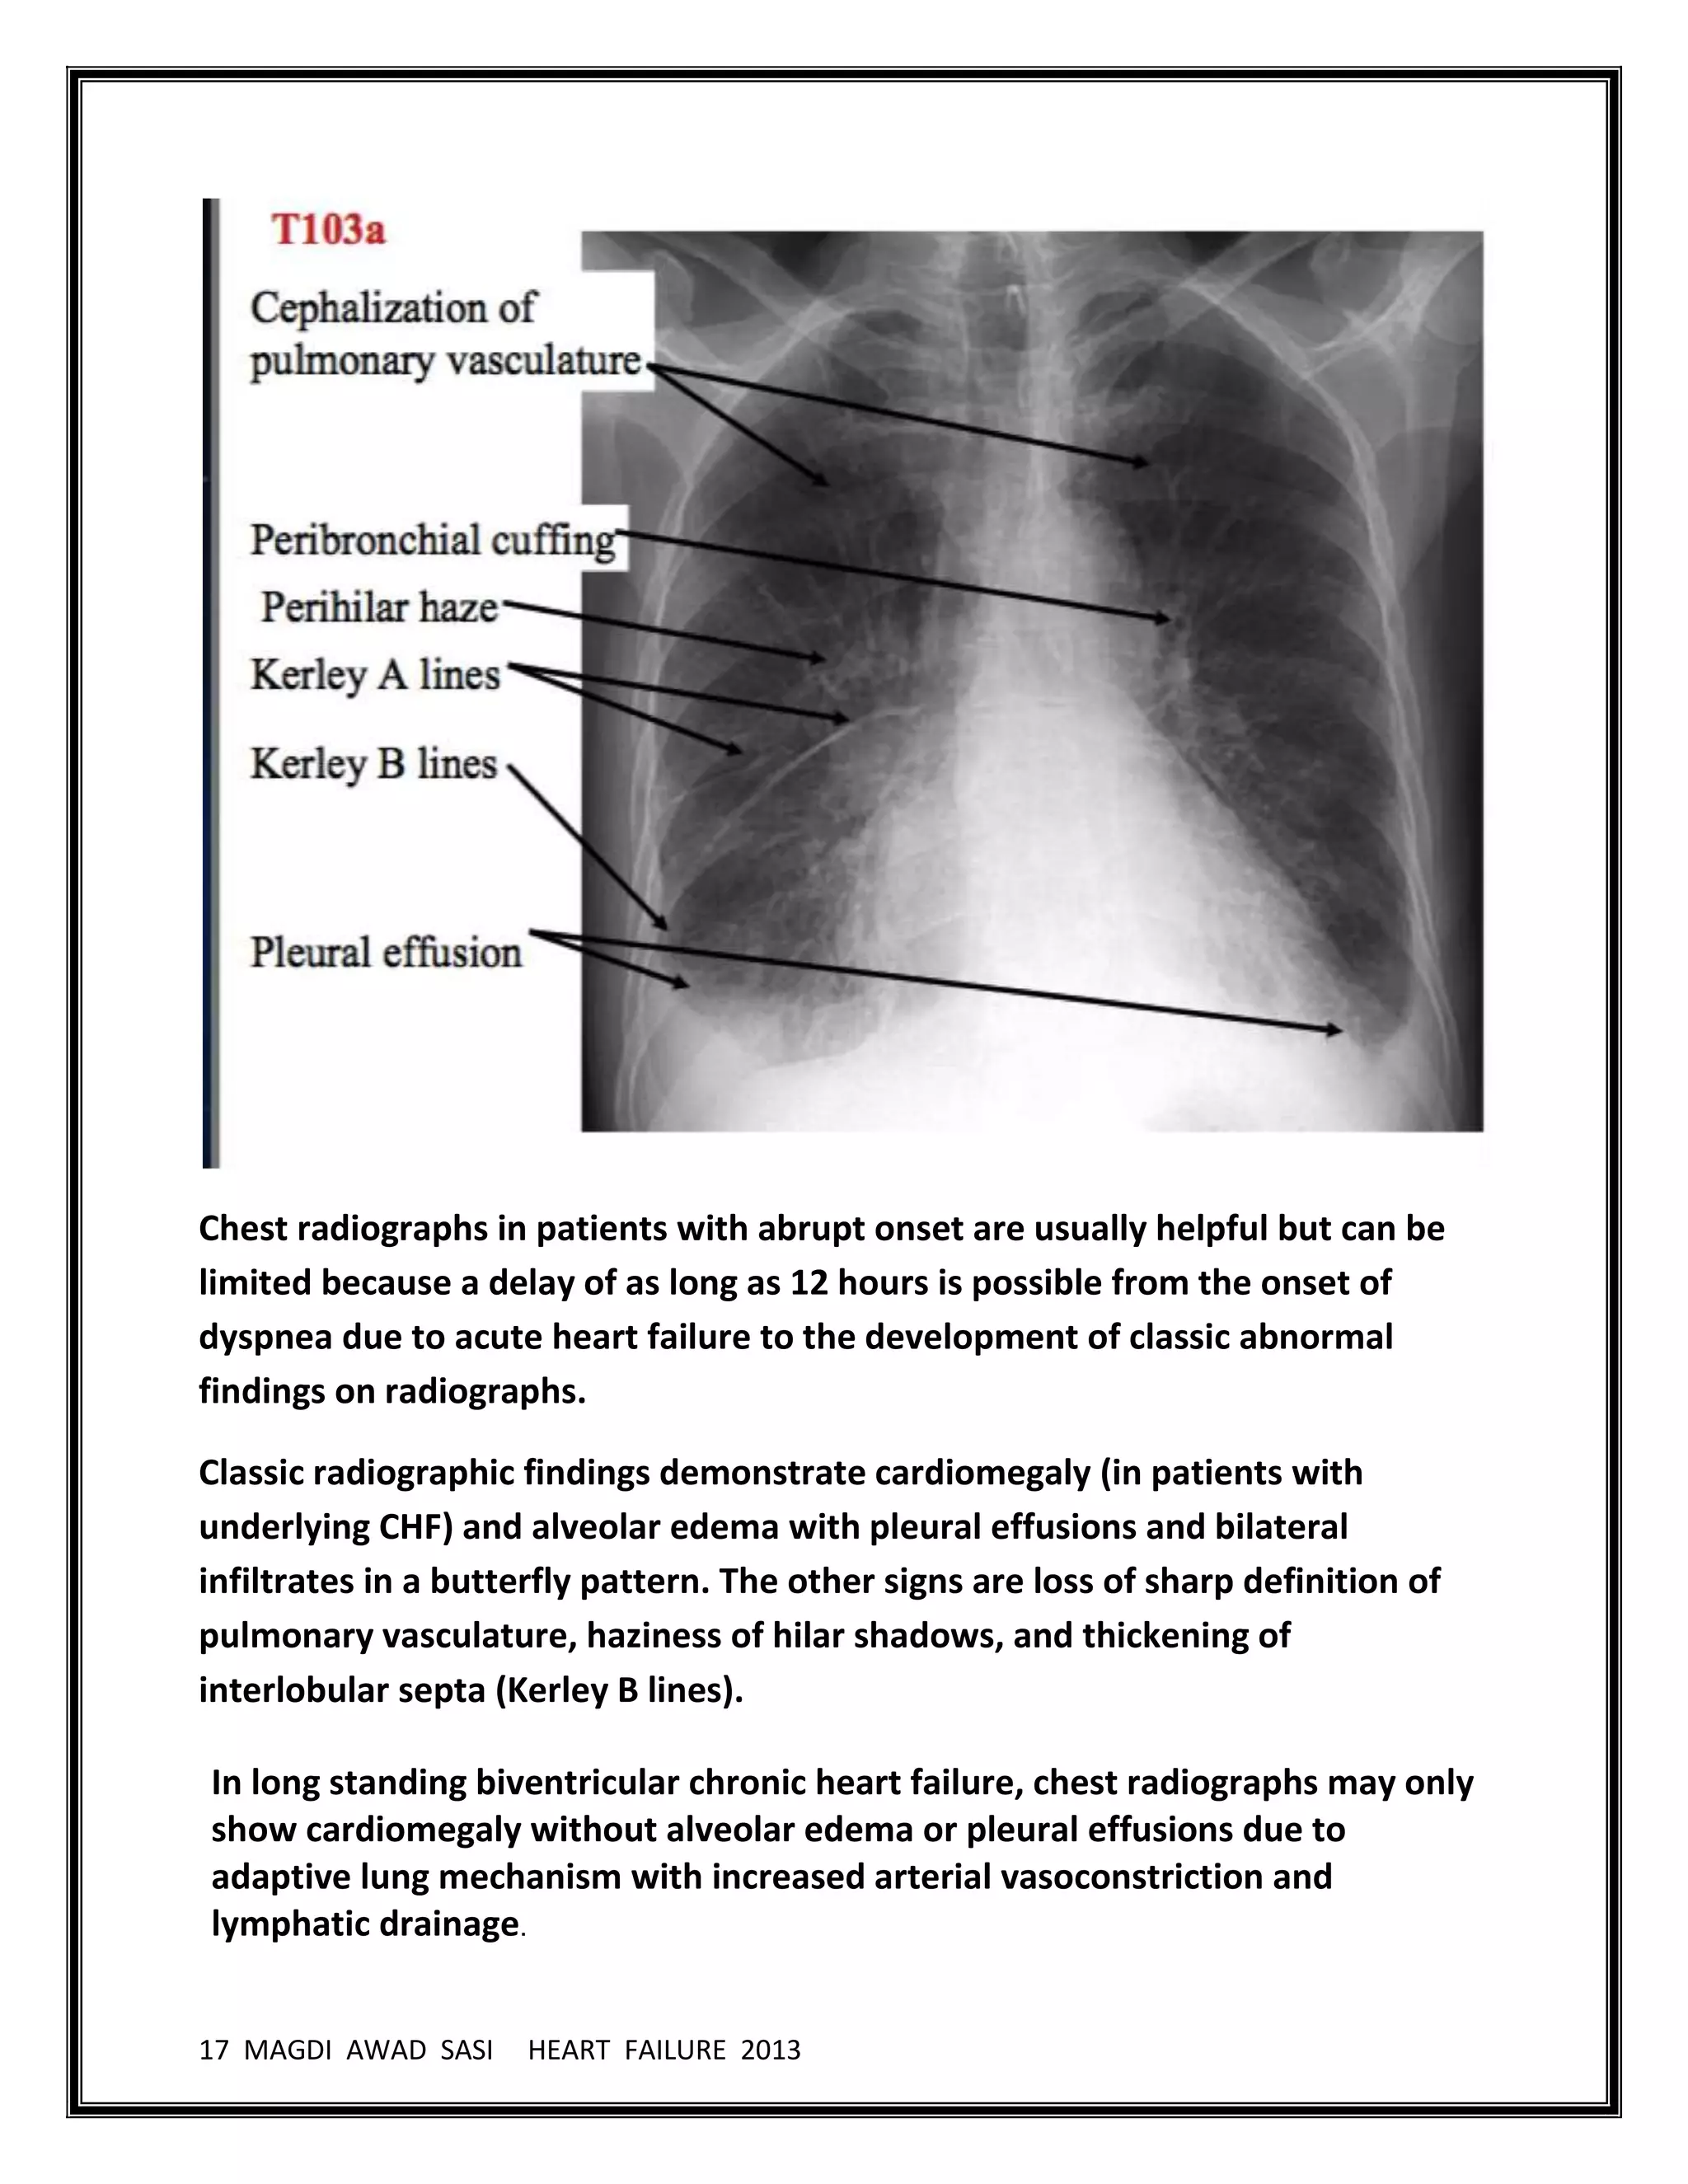

Echocardiogram

Chamber enlargement

Wall motion abnormalities

Diminished ejection fraction

Possible LVH

Possible valvular problems

Assess diastolic dysfunction